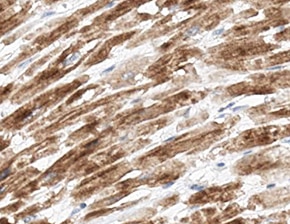

Laminin alpha 2 in Human Heart. Laminin alpha 2 was detected in immersion fixed paraffin-embedded sections of human heart using Mouse Anti-Human Laminin alpha 2 Monoclonal Antibody (Catalog # MAB2143) at 5 µg/mL for 1 hour at room temperature followed by incubation with the Anti-Mouse IgG VisUCyte™ HRP Polymer Antibody (Catalog # VC001). Before incubation with the primary antibody, tissue was subjected to heat-induced epitope retrieval using Antigen Retrieval Reagent-Basic (Catalog # CTS013). Tissue was stained using DAB (brown) and counterstained with hematoxylin (blue). Specific staining was localized to cell membranes in cardiomyocytes. View our protocol for IHC Staining with VisUCyte HRP Polymer Detection Reagents.